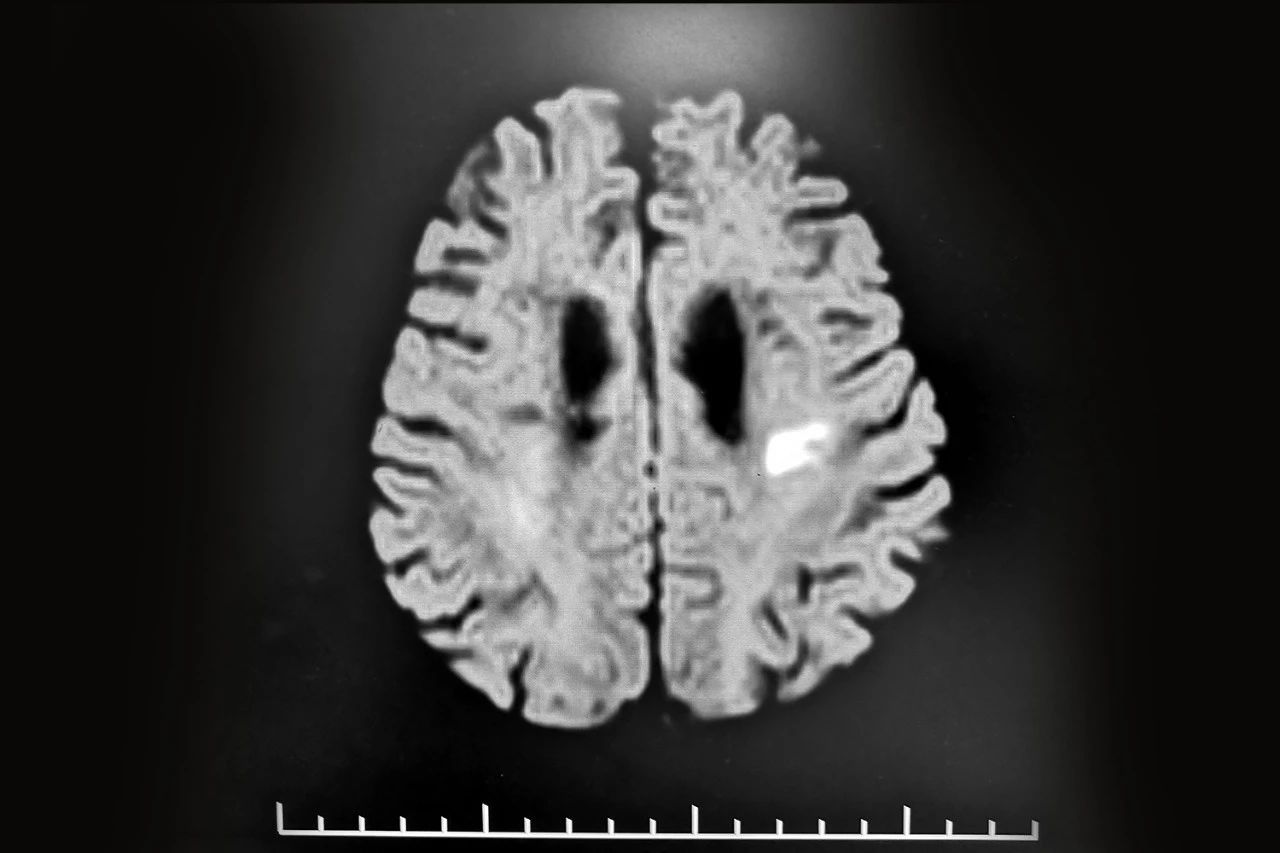

超大规模研究!PM2.5对帕金森、阿尔兹海默症的长期影响

“不少人对帕金森病的印象可能停留在‘抖手’上,人们对帕金森病的了解多是震颤、肢体僵硬、行动迟缓、姿势平衡障碍等运动方面的症状,...